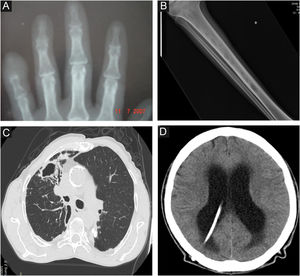

Radiological images in human sporotrichosis. (A) Osteoarticular form – resorption of the distal phalanx of the little finger caused by a cat bite (plain radiography). (B) Systemic form with osteoarticular manifestation – osteolytic lesions in the tibial medulla by hematogenous spread in a patient with systemic sporotrichosis and AIDS (plain radiography). (C) Pulmonary – cavity in the upper lobe of the right lung and extensive pulmonary opacity with a fibroretractile appearance (computed tomography). (D) Neurosporotrichosis – meningitis in a patient with systemic sporotrichosis and AIDS. Increase in the dimensions of the ventricular system, mainly in the supratentorial region (tetraventricular hydrocephalus), ventriculoperitoneal shunt catheter (computed tomography).

OsteoarticularIt is the most common clinical manifestation after the skin and the mucosa. The osteoarticular involvement usually occurs from the contiguous skin lesion, and is usually unifocal.44 In these cases, the most important risk factors are lesions in the extremities, especially hands and feet, due to the close anatomical proximity between the skin and the osteoarticular system and osteometabolic frailty, especially in the elderly or chronic users of corticosteroids; and bite wounds, due to the greater depth of the inoculum (Fig. 3A).

With osteoarticular involvement ‒ The involvement of the osteoarticular system through the hematogenous route is usually associated with invasive and intensely disseminated disease, particularly in AIDS patients, but it can also be seen in other immunosuppressive conditions.45 In these cases, there is multifocal involvement of long bones, with osteolytic lesions (Fig. 3B). Clinically, there is pain and functional limitation, and there may rarely be inflammatory signs, considering the low potential of inflammatory cell immune response in these patients.

Primary pulmonary ‒ patients have an underlying lung disease, usually smokers with COPD, with one or multiple cavitated lesions, associated with lung parenchyma fibrosis and architectural destruction (Fig. 3C).

Neurological (neurosporotrichosis) ‒ Involvement of the central nervous system (CNS) by Sporothrix spp. is a rare and severe condition. It usually occurs in more invasive pictures of the disease, particularly associated with AIDS, by hematogenous spread through the blood-brain barrier. In addition to host susceptibility, some Sporothrix species show greater virulence with neurotropism, especially S. brasiliensis strains. In neurosporotrichosis, subacute to chronic meningitis is usually present, although meningeal irritation may be mild or asymptomatic when there is significant depletion of cellular immunity (Fig. 3D). Early lumbar puncture to investigate CNS involvement should be routine in patients with AIDS and clinical signs of systemic sporotrichosis.58 On the other hand, neurological symptoms with more overt signs of meningismus may occur in immune reconstitution inflammatory syndrome (IRIS), which facilitates diagnostic suspicion.59 In neurosporotrichosis, the cerebrospinal fluid may be clear. There is an increase in cellularity at the expense of mononuclear cells, hyperproteinorrhachia, and hypoglycorrhachia. Due to the low parasitic load of Sporothrix spp. in the CNS, the isolation and identification of the fungus in culture samples is rare. In these cases, molecular methods seem to be promising for diagnostic investigation.